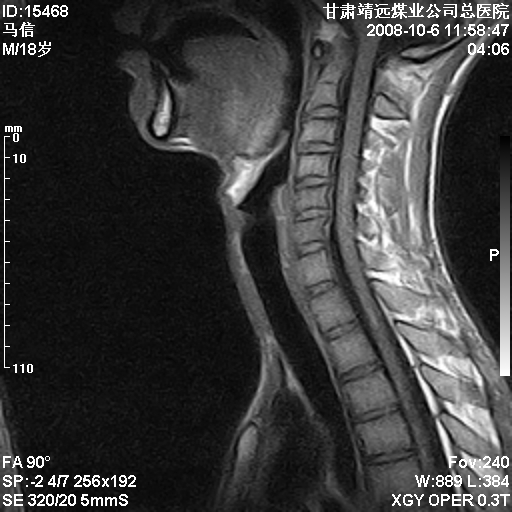

标题: MRI1827:颈椎内异常信号,是不是占位。

患者18岁,学生,在玩耍中受伤来检查,患者喜欢打篮球。颈椎内异常信号影,我们考虑占位,但是不像占位,又考虑硬膜囊的增厚,大家关建看颈椎椎管内的那个异常占位信号

腰椎的改变是不是正常发育的改变,还是打篮球的长期慢性损伤。

后纵韧带增厚,颈2/3、3/4、4/5、5/6椎间盘变性、突出;椎体有旋转,提示椎小关节有问题;腰椎间盘变性,许莫氏结节。

后纵韧带增厚,颈2/3、3/4、4/5、5/6椎间盘变性、突出;椎体有旋转,提示椎小关节有问题。腰椎诸椎体终板骨骺炎可能性大!支持!